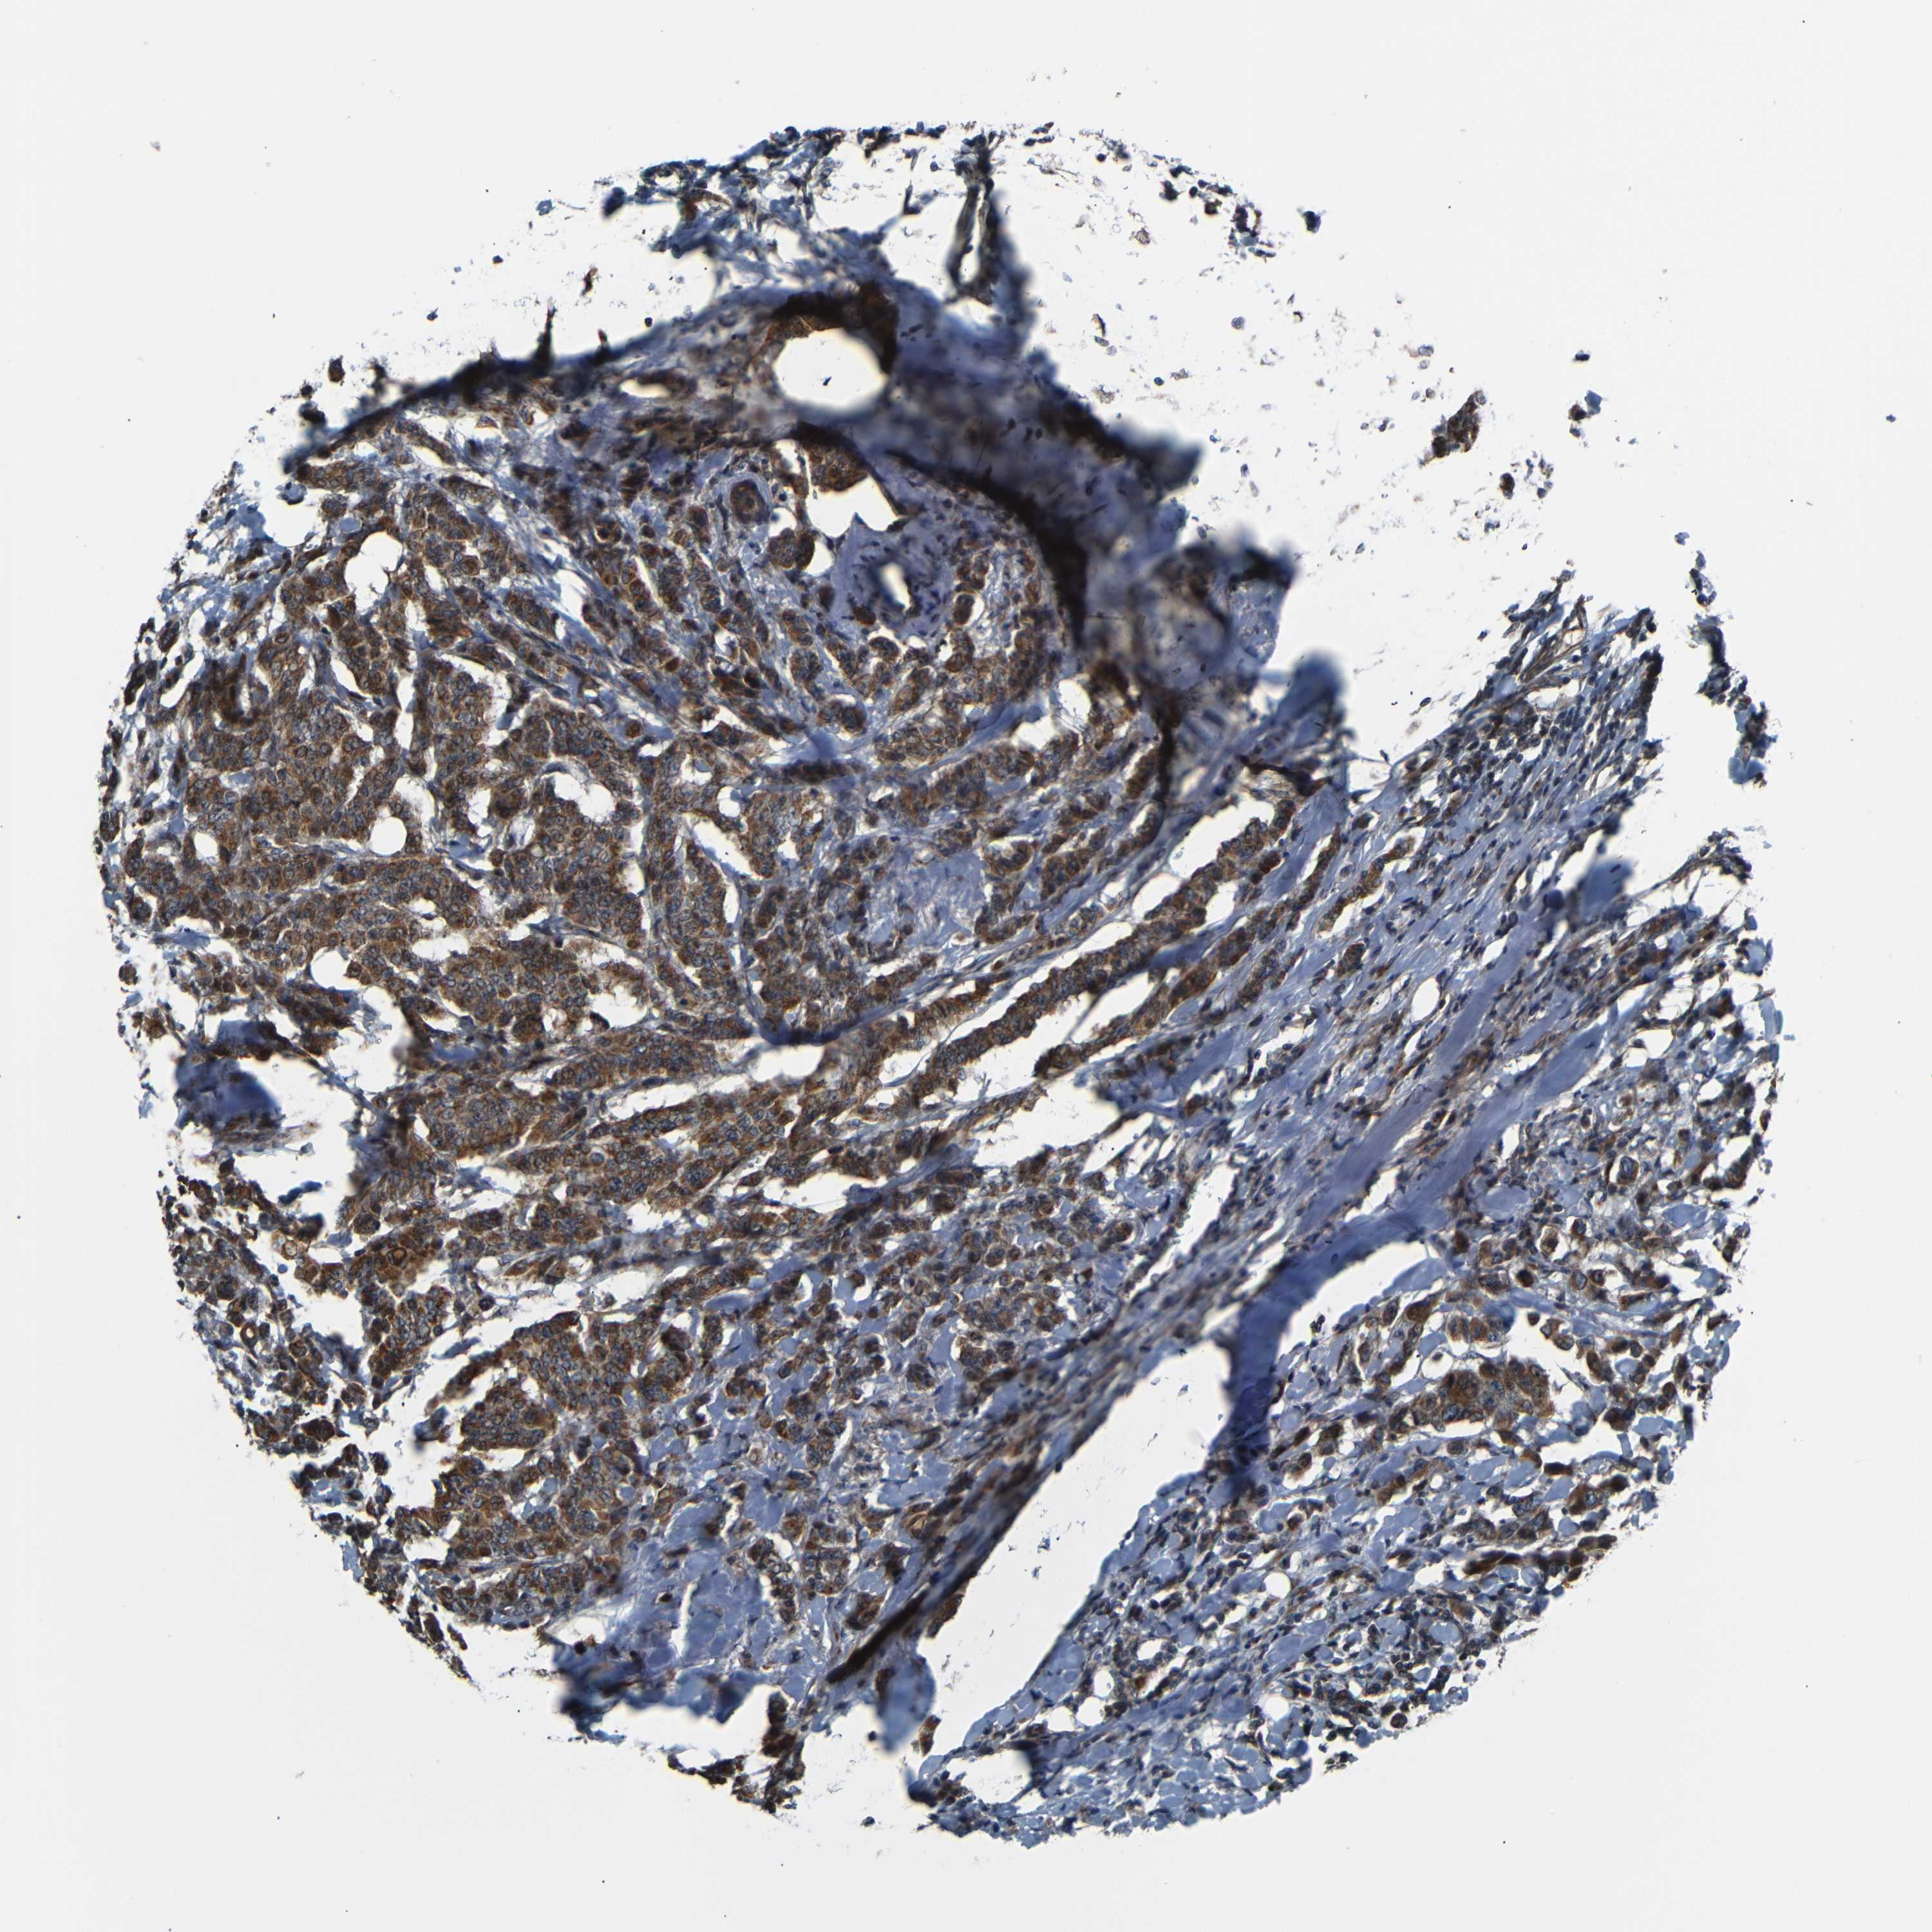

BRCA TCGA BRCA VALIDATION PROTEIN EXPRESSION

ANTIBODIES

AND

VALIDATION